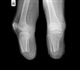

Gout is a type of inflammatory arthritis caused by the crystallization of uric acid within the joints and other tissues. Those with gout experience severe pain and swelling, with the majority of cases affecting the feet. A study published last month in the ACR journal, Arthritis & Rheumatism, shows that doctor-diagnosed gout has risen over the past twenty years and now affects 8.3 million individuals in the U.S. Previous studies have shown that chronic gout contributes to changes in patients' gait parameters, which is consistent with pain avoidance strategy, and likely leads to impaired foot function.

"We found that gout patients in our study often wore improper footwear and experienced moderate to severe foot pain, impairment and disability," explains Professor Rome. Roughly 56% of patients made good footwear choices by wearing walking shoes, athletic sneakers, or oxfords. Of the remaining patients, 42% wore footwear that are considered poor and included sandals, flip-flops, slippers, or moccasins; 2% wore boots which are considered average; and none wore high-heeled shoes.

Characteristics of poor footwear included improper cushioning, lack of support, as well as inadequate stability and motion control. Those gout patients who wore poor shoes or sandals reported higher foot-related impairment and disability. More than half of all participants wore shoes that were 12 months or older and showed excessive wear patterns. Factors study participants identified as important for selecting footwear included comfort (98%), fit (90%), support (79%), and cost (60%).